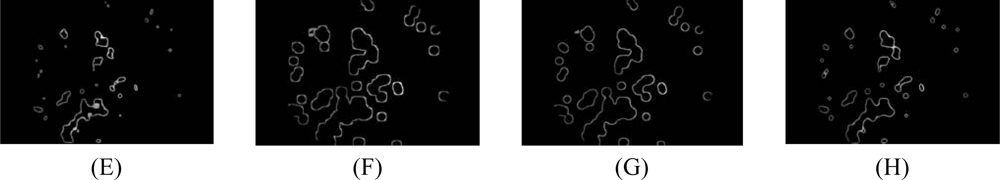

- 4.5 A number of neighboring white pixels of the resulting image from the process 4.1 – 4.4 is counted using a window size of 17 × 17 to form our final feature, namely an image of the number of edge pixels as shown in Figure 3D:where area is the number of pixels in the region and perimeter is the total number of pixels around the boundary of each region.